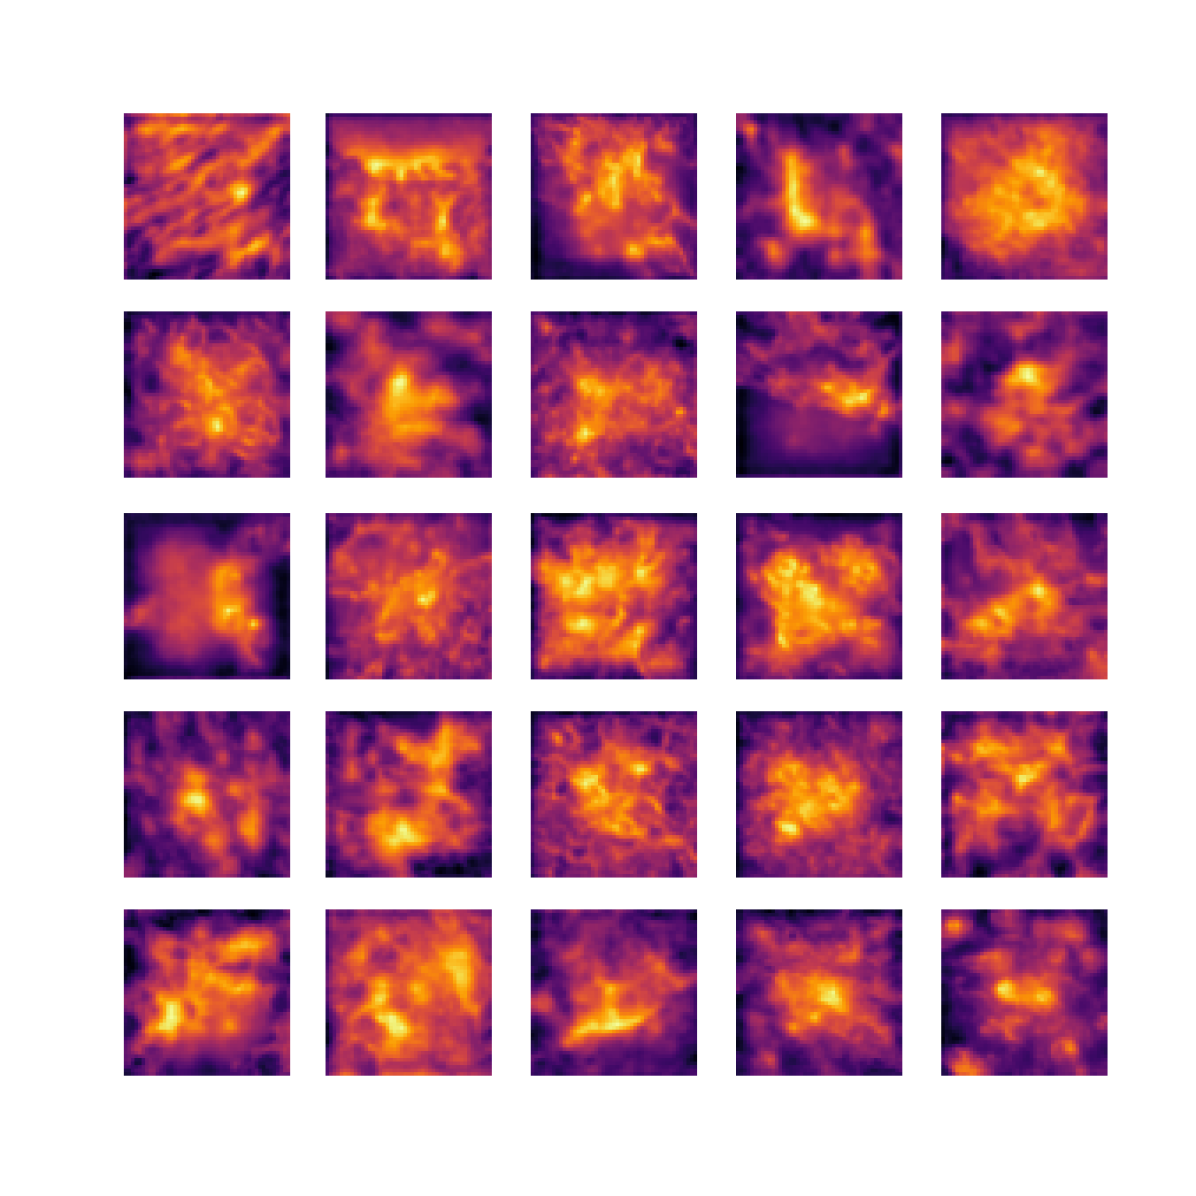

We also analyse the activation maps for each model using GradCAM as described in section S3. This offers more insight into the areas of the image which are contributing most heavily to the models’ representations. In Figure 4(b) we present some representative examples, however, a larger selection which was chosen at random is presented in Figures S10 to S25. The larger selection makes it easier to see the emergent patterns, including that privileged Siamese models tend to mainly identify features which are strongly present in both inputs, while unprivileged Siamese models tend to learn more diffuse features that are not specific to one cell phenotype or image region. TriDeNT ♆ incorporates both sets of features, learning both features specific to the privileged data and more the general features associated with unprivileged Siamese networks.

We can see in Figure 4(b) panel A that for ERG, the privileged Siamese model focuses almost exclusively on any nuclei which could be endothelial cells. As there are very few endothelial cells in the dataset, it could be an effective strategy to identify anything that could potentially be an endothelial cell to minimise the difference between the representations of the H&E model and the IF mask model. In the corresponding unprivileged Siamese image, we see that the model identifies some of these nuclei, albeit less strongly, but also focuses heavily on the other tissue and even the background, while strongly fixating on two spots of debris in the center of the image. This model has less ‘incentive’ to learn the weak features related to endothelial cells as these occur rarely and are not easy to detect, while more generic strong features such as the presence of connective tissue and the prevalence of background are more common and predictable from augmented images. We see that TriDeNT ♆ combines these two feature sets, strongly identifying nuclei while also identifying the connective tissue.

In panel C we see a similar pattern, with the privileged Siamese model fixating solely on the nuclei, while the TriDeNT ♆ model takes a more balanced approach. The unprivileged Siamese model appears to focus on a single cluster of nuclei while neglecting others, and similarly identifies an area of fibroblasts with its distinctive pattern but does not others.

In contrast to panels A and C which represent models with poor privileged Siamese results, panels B and D represent models whose privileged Siamese results were comparable to both TriDeNT ♆ and even the supervised baseline. It is therefore interesting to note that there are far more similarities between the privileged Siamese and TriDeNT ♆ models in both cases. Particularly in panel B, TriDeNT ♆ and the privileged Siamese model return virtually identical heatmaps, with both strongly identifying epithelial nuclei and neglecting the same areas of connective tissue. The unprivileged model in this case appears to focus solely on the centre of the image, giving a significantly different heatmap to the other panels.

Panel D again shows the previous pattern, with the privileged Siamese model identifying the features strongly present in the privileged data – fibroblasts – while neglecting the nuclei present. TriDeNT ♆ also strongly identifies the connective tissue, but, unlike the privileged Siamese model, does not completely neglect the nuclei. The unprivileged Siamese model primarily identifies background, and does not appear to identify the nuclei in this example.